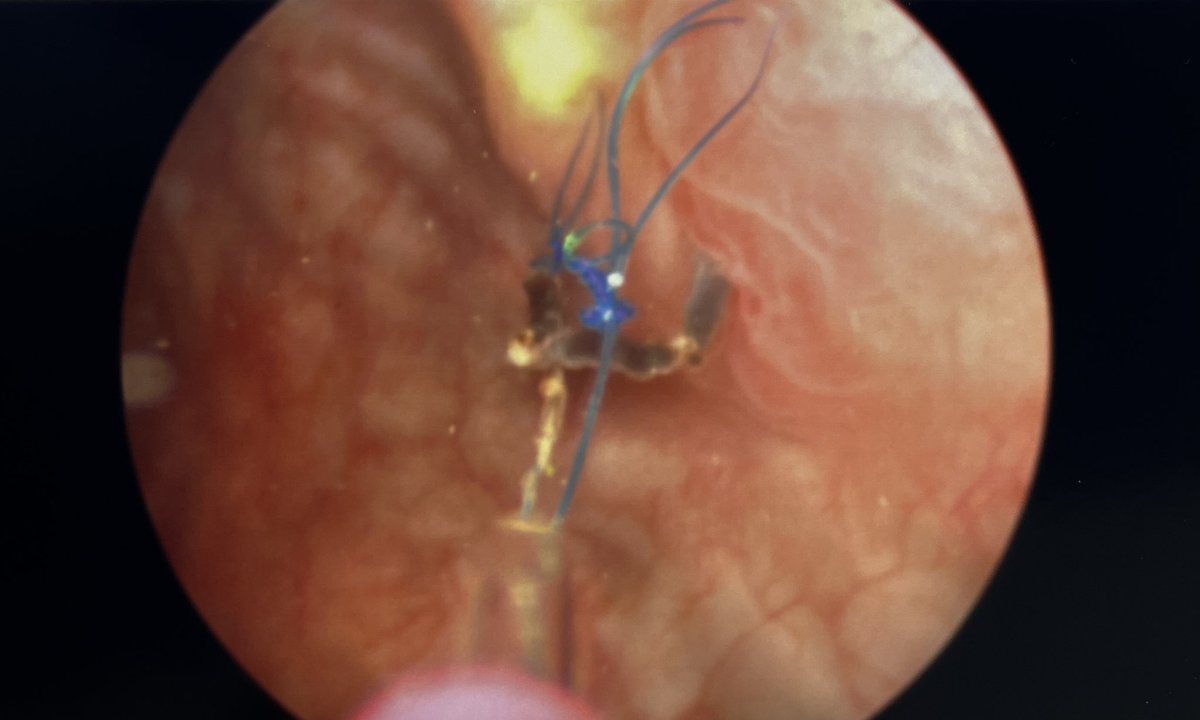

Kidney transplant recipient referred for bladder calculus. Looks like prolene at the anastomosis from nearly 30 years ago! Reminder to always use absorbable suture in the GU tract!